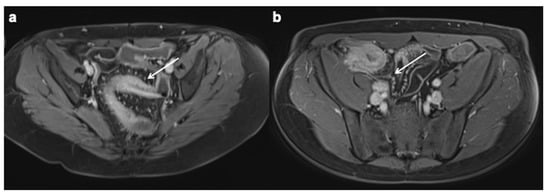

11. Imaging Findings Associated with Penetrating CD Inflammation and Complications

| Imaging findings associated with penetrating CD and complications |

| Sinus tract |

Fistula

|

| Inflammatory mass |

| Abscess |

- Oto, A.; Schmid-Tannwald, C.; Agrawal, G.; Kayhan, A.; Lakadamyali, H.; Orrin, S.; Sethi, I.; Sammet, S.; Fan, X. Diffusion-weighted MR imaging of abdominopelvic abscesses. Emerg. Radiol. 2011, 18, 515–524. [Google Scholar] [CrossRef]

- Schmid-Tannwald, C.; Agrawal, G.; Dahi, F.; Sethi, I.; Oto, A. Diffusion-weighted MRI: Role in detecting abdominopelvic internal fistulas and sinus tracts. J. Magn. Reson. Imaging 2011, 35, 125–131. [Google Scholar] [CrossRef]

- Barat, M.; Hoeffel, C.; Bouquot, M.; Jannot, A.S.; Dautry, R.; Boudiaf, M.; Pautrat, K.; Kaci, R.; Camus, M.; Eveno, C.; et al. Preoperative evaluation of small bowel complications in Crohn’s disease: Comparison of diffusion-weighted and contrast-enhanced MR imaging. Eur. Radiol. 2018, 29, 2034–2044. [Google Scholar] [CrossRef]